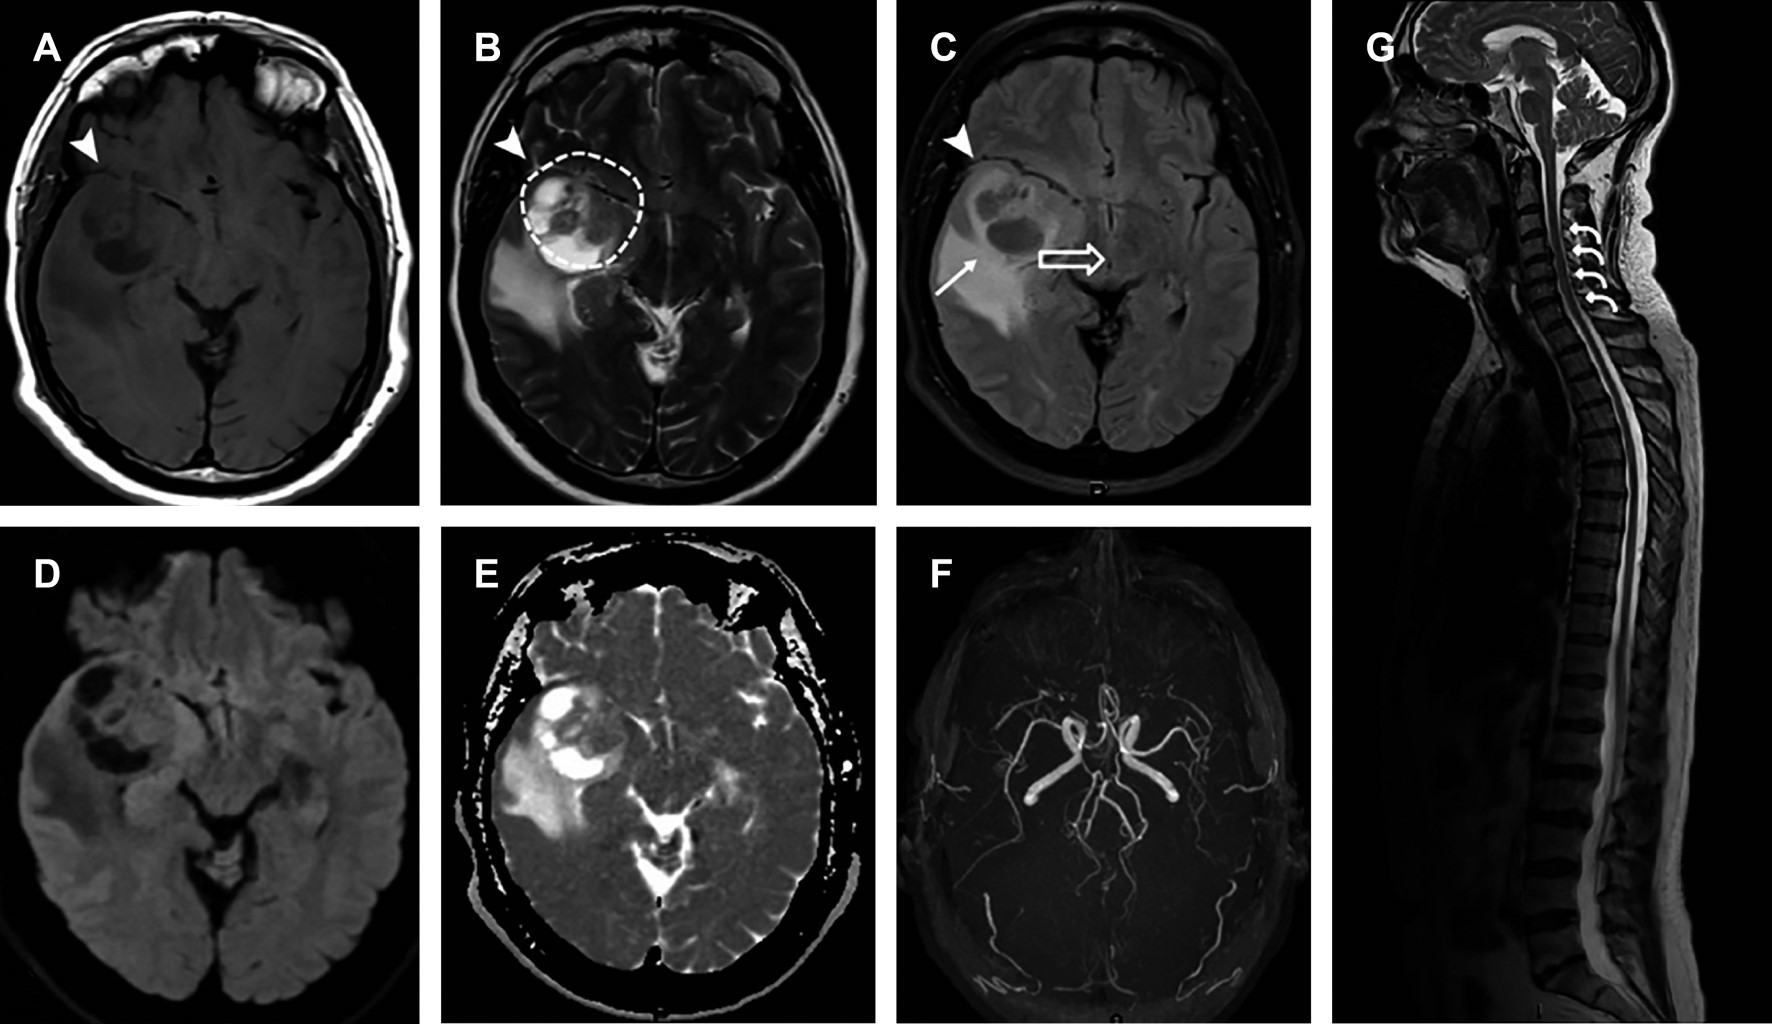

Paciente masculino de 57 años consulta a neurocirugía por cefalea persistente de intensidad 10/10 según la escala verbal numérica del dolor, sin déficit en funciones neurocognitivas y con escasa mejoría tras el uso de analgésicos. La resonancia magnética (Figuras 1 y 2) revela una lesión temporal derecha de 5.6 cm, sugiriendo glioblastoma como diagnóstico principal. Se realiza craniectomía temporal derecha con durotomía, disección subpial y exéresis del tumor en bloque, seguido de hemostasia y cierre. Los estudios histopatológicos e inmunohistoquímicos confirman gliosarcoma grado 4 (Figura 3).

Las manifestaciones clínicas incluyen cefalea, mareos, náuseas, vómitos, debilidad en las extremidades que induce una marcha inestable, cambios en la agudeza visual y en el estado mental.2,3 En las imágenes de resonancia magnética se observa como una masa supratentorial con periferia heterogénea irregular en T1 y T2, principalmente en el lóbulo temporal. No obstante, el diagnóstico definitivo depende del resultado histopatológico.2-4 El tratamiento comprende resección quirúrgica, radioterapia y quimioterapia, con un pronóstico desfavorable y una supervivencia media de 16.8 meses tras el diagnóstico.4,5

El gliosarcoma, variante extraordinariamente rara del glioblastoma (IDH) de tipo agresivo,1,2 se caracteriza por la coexistencia de componentes gliales y mesenquimales, por lo general ubicados en la región supratentorial y lóbulo temporal.2,3 La resonancia magnética muestra un patrón heterogéneo con imágenes hipo-hiperintensas de contornos regulares. En la espectroscopia, los valores máximos de N-acetilaspartato (NAA), colina (Cho) y creatina (Cr) aumentan significativamente; sin embargo, el diagnóstico basado únicamente en características de la imagen sigue siendo un desafío.2-4 Dada la escasa cantidad de casos reportados, el tratamiento se asemeja al del glioblastoma multifocal (resección quirúrgica, radioterapia y quimioterapia adyuvante), pero el pronóstico sigue siendo desalentador, con una supervivencia media de 16.8 meses tras el diagnóstico.3-5